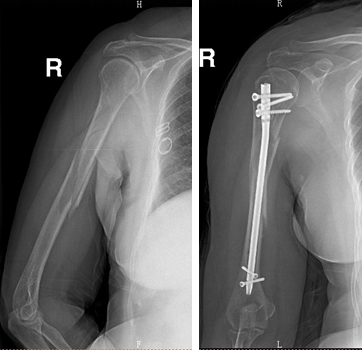

女性,63岁,摔伤致右肱骨干骨折

术前                            术后